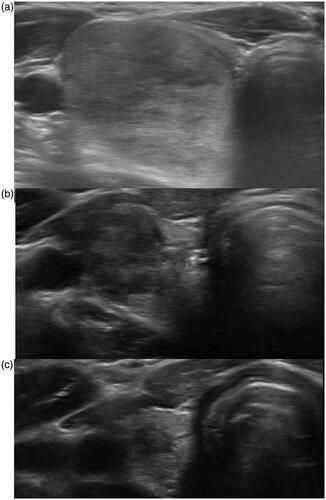

I am a clinical thyroidologist That means I evaluate patients for cancer. I do ethanol ablations of complex benign cystic solid nodules and radiofrequency RFA